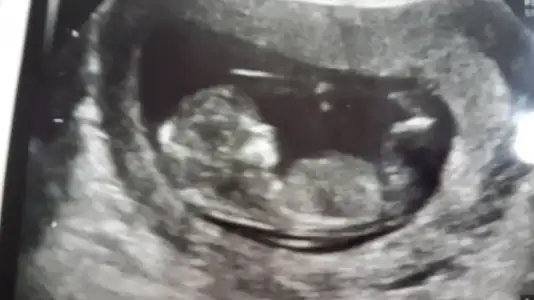

dr soylemeden siz gorun genital nub teorisi ( bebegin cinsiyeti)

12 haftalik canim

Kizlar tahmininiz ne, doktor bir ay sonra kesin belli olur dedi bisey soylemedi ama cok merak ediyorum, anlasiliyormu resimden ben anlamadim